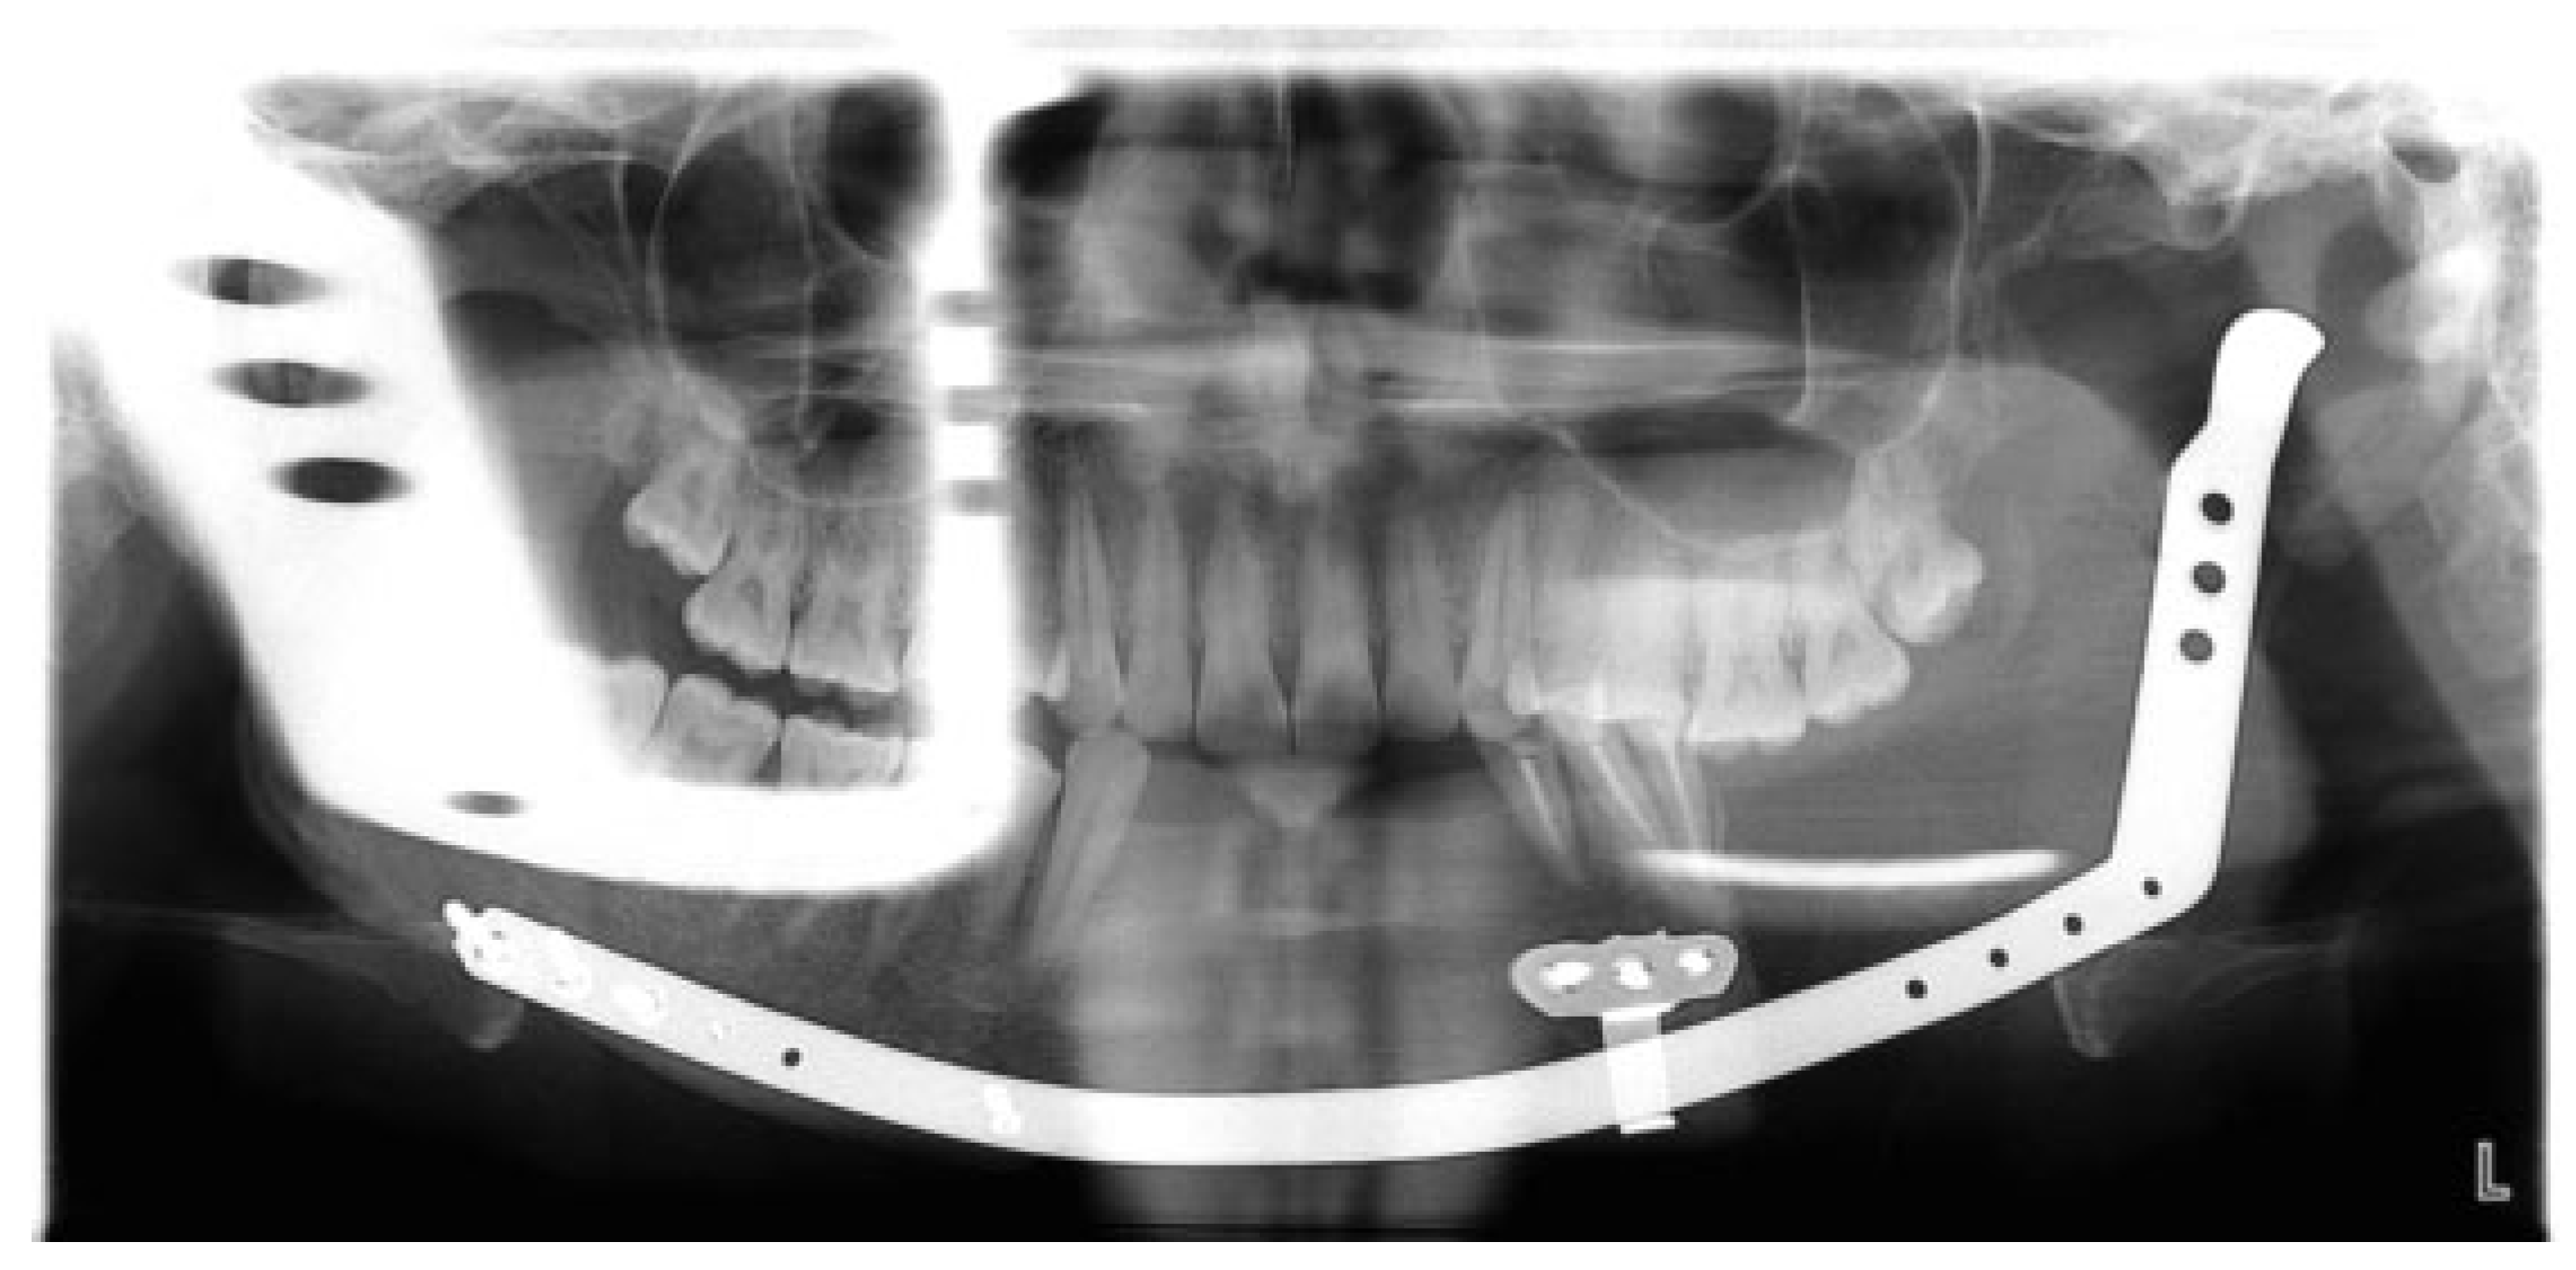

Figure 15.

Case 2. Orthopantomogram view showing the formed regenerate post consolidation.

The existing reconstruction plate was removed and the device was assembled and fixed in situ through a combined oral and extraoral approach (Figure 11). After a latency period of 7 days, activation was performed for a period of 28 days until the transport disc reached the mandibular body region. A consolidation period of 2 months was felt to be mandatory and only the oral component of the appliance was removed (Figure 12, Figure 13, Figure 14 and Figure 15).